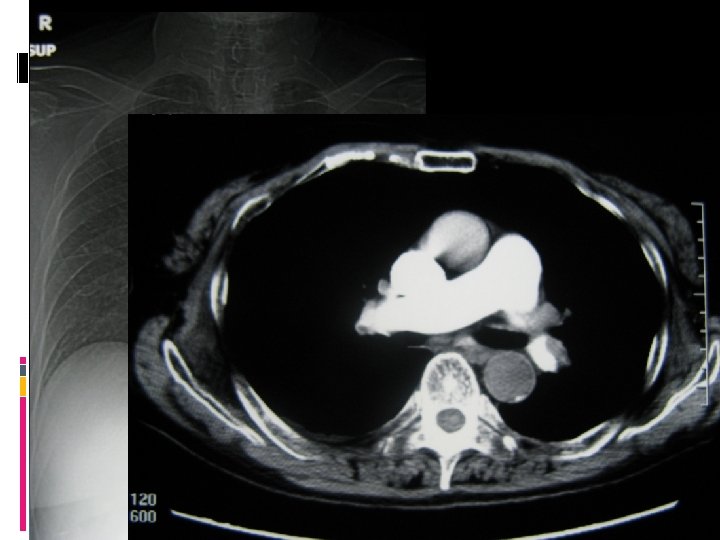

Diagnosis of acute pulmonary embolism in critically ill

Recommendations Remove central venous catheters as soon as possible Low threshold for CT pulmonary angiogram for unexplained hypoxaemia Consider pharmacological prophylaxis after balancing the risks and benefits